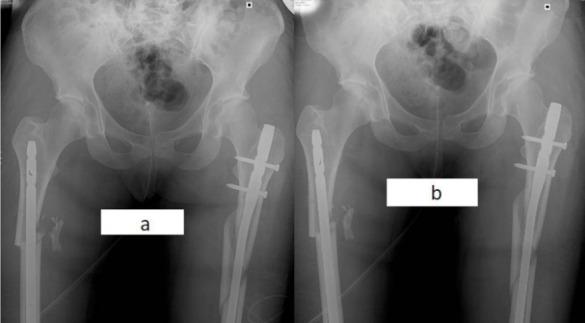

Rotational malalignment in femoral nailing: prevention, diagnosis and surgical correction.

malrotation is very common after femoral nailing. The exact definition of a malrotated femur is controversial, but it is widely agreed that a rotational malalignment <10° is considered normal while >30° is a deformity which requires correction. The complaints of the patients with a malrotated femur can be various and can involve the hip, the knee or below the knee. The ability to compensate for the deformity while standing and walking may decrease the symptoms. Surgical correction is feasible with many techniques and devices: the procedure involving derotation, changing the locking screws and maintaining the nail is safe, reproducible and relatively easy.

prevention of malrotation during femoral nailing is the cornerstone of successful operation outcomes. If rotational malalignment is suspected, prompt diagnosis and adequate surgical treatment are mandatory to overcome this common complication.